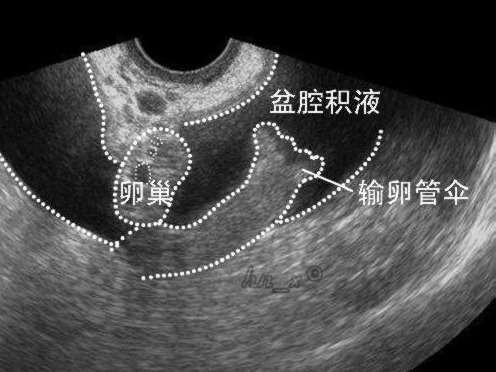

1、妇科炎症导致:病理性的妇科盆腔积液多是盆腔炎附件炎或子宫内膜异位症引起的。

4、其他疾病原因:也可能由结核或者肿引起的,也有少数因宫外孕破裂、黄体破裂、盆腔脓肿、巧克力囊肿、卵巢癌引起。